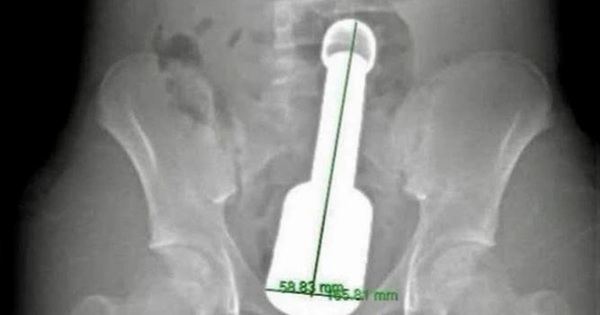

A 15-year-old boy in Hanoi was admitted to the emergency room after a metal rod became stuck in his rectum. This incident raises alarms about the significant gaps in sexual education.

Metal Rod Lodged in Rectum: Adolescence and the Mindset of 'Let’s See What Happens'. A 15-year-old boy in Hanoi was rushed to the hospital after a metal rod became lodged in his rectum. This incident highlights significant gaps in sexual education. This article is edited in a practical format for general readers, highlighting clinical context, warning signs, risk groups, and safe care pathways. It also clarifies when to seek medical attention, how to coordinate with clinicians, and how rehabilitation planning can reduce long-term complications.